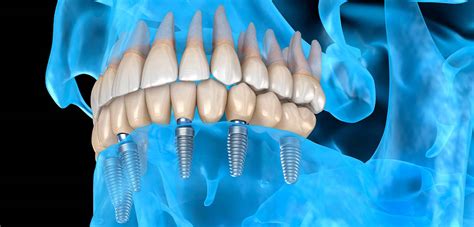

Después de analizar varias alternativas de tratamiento, se determinaron dos fases quirúrgicas y una fase protésica: en una primera fase se decidió realizar extracciones múltiples con preservación de reborde y elevación de piso del seno maxilar bilateral; una vez que se cumplieron los tiempos de integración de los injertos óseos se planea la segunda fase que consistió en la colocación de 12 implantes endoóseos; 6 en el maxilar y 6 en la mandíbula; finalmente en la tercera fase o de rehabilitación donde se colocaron 2 prótesis fijas implantoretenidas.

El buen control glicémico del paciente nos permitió realizar la cirugía de colocación de implantes con los cuidados preoperatorios ya mencionados, así que se realizó un colgajo de espesor total en mandíbula, se verificó el asentamiento de la guía quirúrgica tomográfica la cual fue estabilizada con tornillos de fijación, se inició el protocolo de fresado obteniendo los lechos quirúrgicos y se colocaron seis implantes de conexión externa de diámetro regular distribuidos estratégicamente en las zonas de laterales, primeros premolares y primeros molares, con un torque de inserción mayor a 35N; los colgajos fueron aproximados con sutura Vycril 4-0. Un mes después se realiza el mismo procedimiento en la arcada superior.